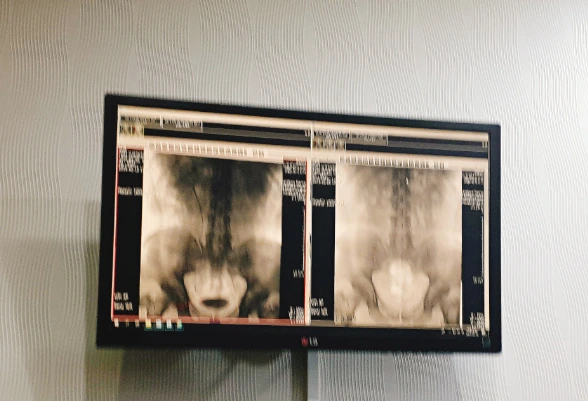

옷을 갈아입고 동일하게 엑스레이를 찍는다.

주사액을 몸에 주사하고, 5분 7분 엑스레이를 더 찍는다.

엑스레이 결과

무언가 의심이 있어서 몇 번 찍으셨다고 한다.

엑스레이상으로는 깨끗하니 마지막으로 초음파 검시로 최종 확인해 보자고 한다.